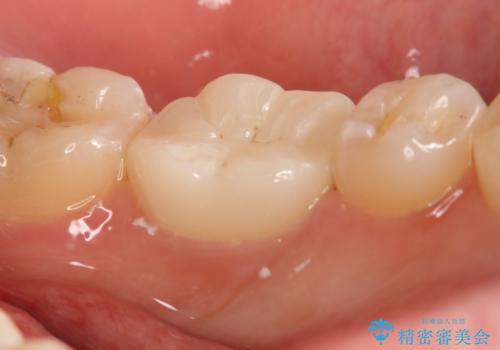

精密根管治療を行なったことで病巣は消失し、腫れや痛みは再発することなく経過は良好です。

被せ物はフルジルコニアクラウンを選択されました。